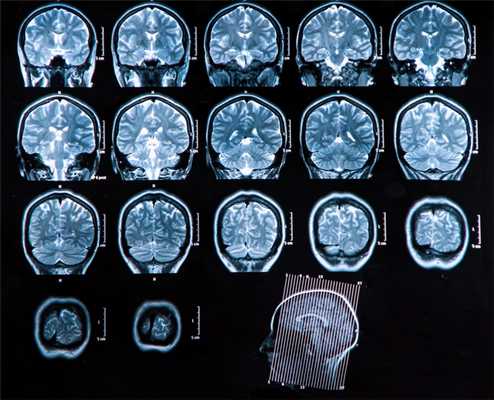

Даже несмотря на то, что вторичные изменения головного мозга не так часто встречаются у пациентов с раковыми опухолями легких, они имеют большое значение, поскольку их наличие приводит к высокому уровню заболеваемости и смертности, чего в некоторых случаях можно избежать или минимизировать путем подбора соответствующего лечения. Поскольку головной мозг характеризуется высоким базовым метаболизмом глюкозы, вторичные очаги в нем могут быть замаскированы, а чувствительность ПЭТ-исследования в обнаружении метастазов - ограничена. В связи с этим, в соответствии с существующими на данный момент протоколами рекомендуется дополнительное использование МРТ. В случаях, когда провести МРТ невозможно, можно сделать КТ с внутривенным контрастным усилением. Это дает схожие результаты с МРТ головного мозга.

Головной мозг

Основной метод оценки непосредственно вещества головного мозга (в том числе первичных опухолей и метастазов) — МРТ с применением контрастного усиления.

Вопросы стадирования (поиск отдаленных метастазов) лучше всего решаются с помощью ПЭТ, в том числе с метионином.

Компьютерная томография используется как дополнительный метод в случае, если требуется оценка состояния костных структур, а также при наличии абсолютных противопоказаний к МРТ исследованию (наличие металла в теле — например, кардиостимулятора, ферромагнитных инородных металлических соединений: пластины, протезы, импланты и т.п.)